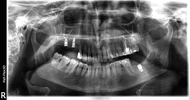

أمراض الأسنان واللثة

اعوجاج الأسنان